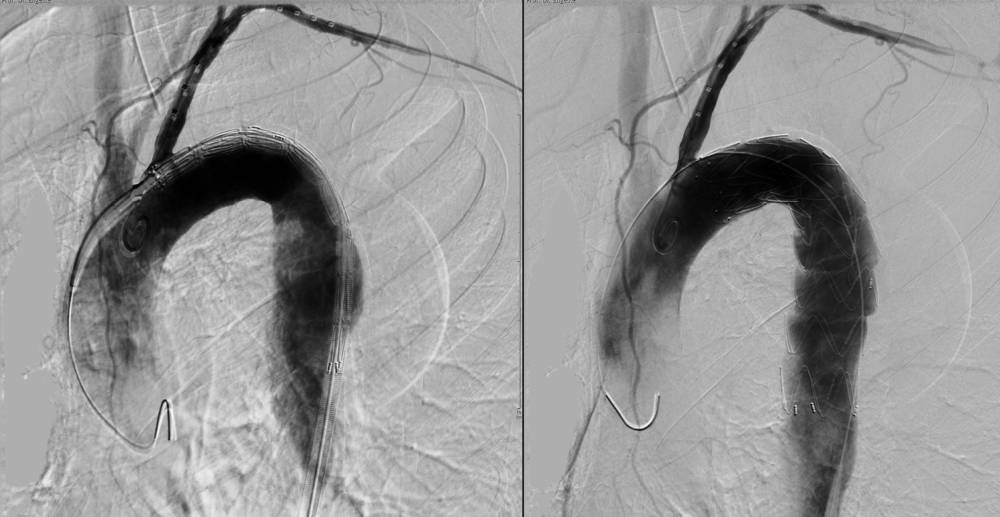

Angiographie (DSA)

Röntgenaufnahme der Aorta mit Kontrastmittel, zeigt den Blutfluss und mögliche Anomalien.

Bei einer Angiographie machen wir die Gefäße mithilfe von Kontrastmitteln unter einer Röntgendurchleuchtung sichtbar. Zugang zu den Gefäßen bekommen wir in der Regel über die linke Ellenbeuge bzw. die rechte oder linke Leiste. Gefäßverengungen können wir über denselben Zugangsweg, z.B. mithilfe spezieller Ballons und Gefäßstützen (sog. Stents), behandeln. Außerdem können wir über den Katheter, der in der zuführenden versorgenden Arterie platziert wird, Chemotherapeutika (transarterielle Chemoembolisation: TACE) injizieren. So können Lebertumore minimalinvasiv behandelt werden. Unsere Abteilung bietet mit der Angiologie das gesamte Spektrum der angiographischen Diagnostik und Intervention an – Eingriffe an gehirnversorgenden Gefäßen ausgenommen. Für eine Angiographie melden Sie sich bitte an der Leitstelle Radiologie bzw. der Leitstelle Angiologie (Standort Neu-Mariahilf).

Vor dem Eingriff sprechen wir ausführlich mit Ihnen über den Eingriff und klären Sie über mögliche Risiken auf. Bitte essen und trinken Sie am Tag des Eingriffs sechs Stunden vorher nichts. Fragen Sie Ihre behandelnde Ärztin bzw. Ihren behandelnden Arzt bezüglich der Einnahme von Tabletten. Unter lokaler Betäubung punktieren wir ein geeignetes Zugangsgefäß. Wir bringen ein Zugangsröhrchen (Schleuse) in ein Gefäß in der Leiste ein und machen den Eingriff über einen Katheter. Abschließend setzen wir an der Punktionsstelle der Arterie ein Verschlusssystem ein und legen einen Kompressionsverband an. Dieser soll zwölf Stunden anliegen, um das Risiko einer Nachblutung in der Leiste zu minimieren. In dieser Zeit müssen Sie Bettruhe wahren. Daher behalten wir Sie bis zum nächsten Tag auf Station.